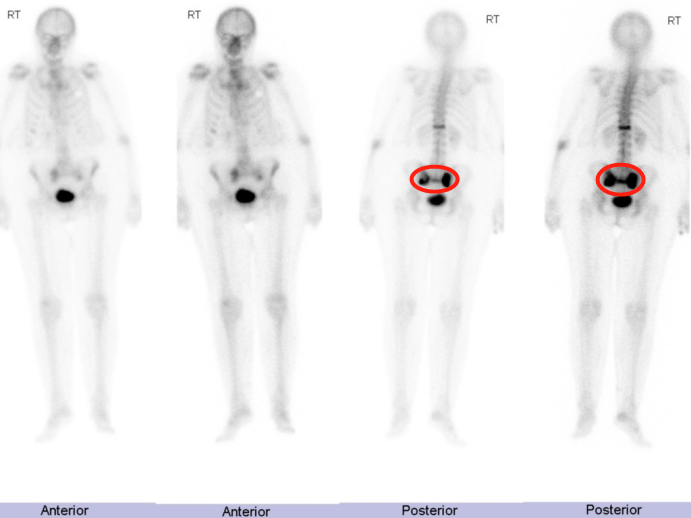

病例展示

本田征象

骶骨机能不全骨折时骨折线通常垂直穿过骶骨翼,平行于双侧骶髂关节,在核医学 SPECT/CT 或 PET/CT 显像(冠状位重建)形似东风本田车标—大写字母「H」,故又称「Honda」征、东风本田征,为骶骨机能不全骨折较特异影像表现。

SPECT/CT 显像见骶骨体及骶骨翼均受累,两侧基本对称,呈典型「H」征;同机 CT 显示骶骨骨质密度增高、骨质硬化改变;敏感度高、特异性稍低。